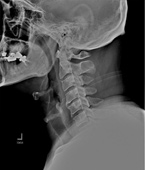

Before

After